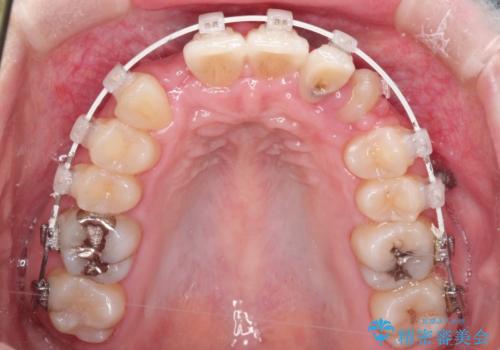

犬歯が変な位置にある 抜歯矯正により正しい位置へ

左上の犬歯が通常の位置より、かなり上方にあり、乳歯の残存と前歯のがたつきがありました。

残った乳歯と上下左右の永久歯を1本ずつ抜歯して、ワイヤーにて矯正することとしました。